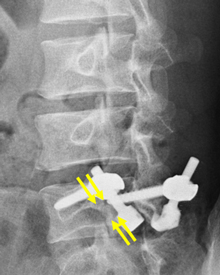

矢印が分離部で骨が離れています。

分離部に骨が移植され骨癒合が

得られています。